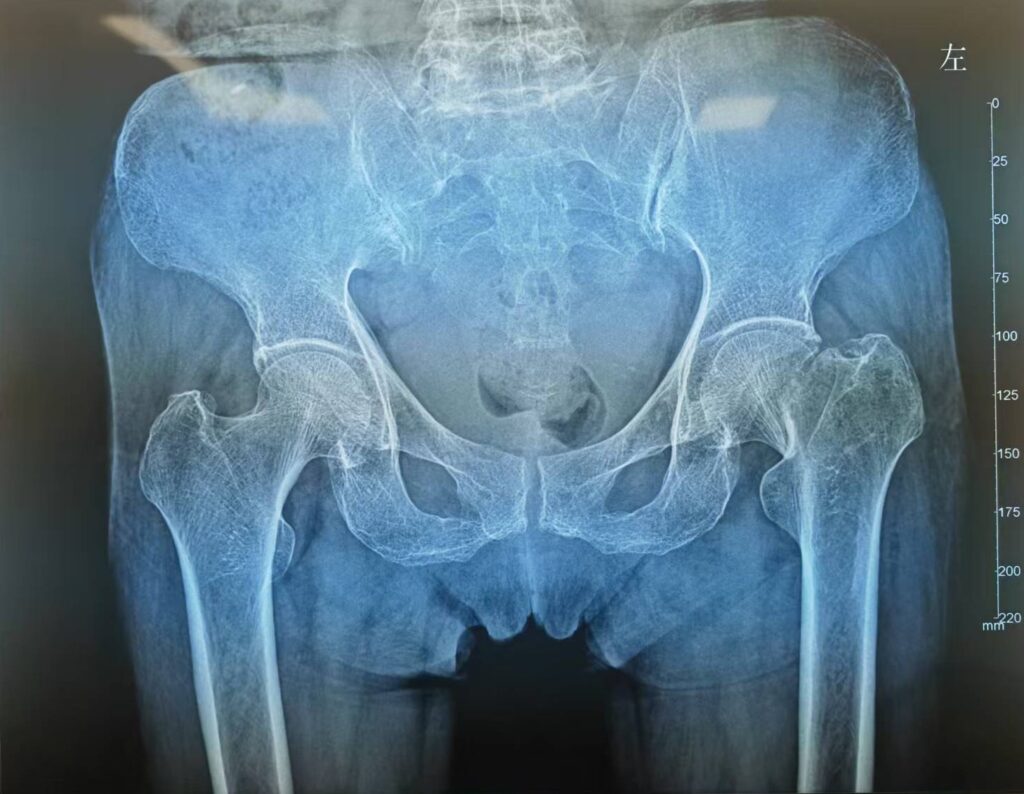

股骨颈骨折人工股骨头置换术(Artificial femoral head replacement for femoral neck fractures)